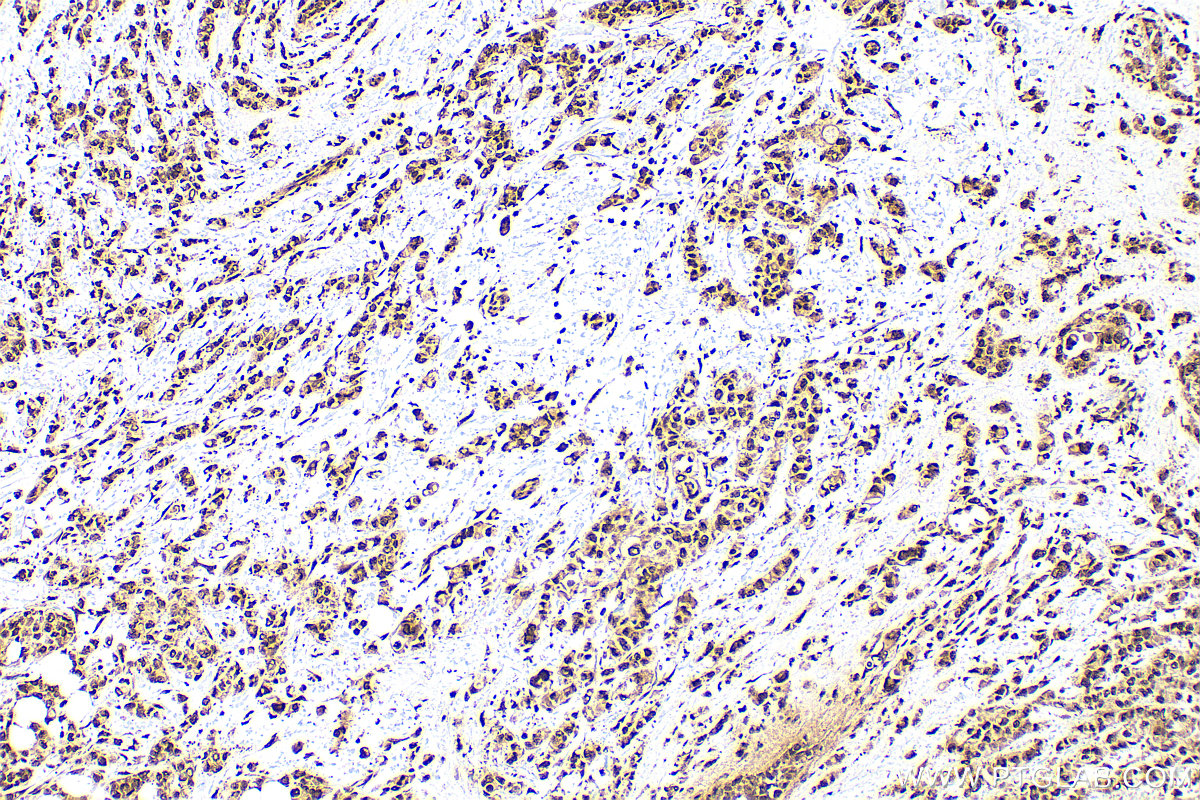

| Positive IHC detected in | mouse brain tissue, human breast cancer tissue, human colon tissue Note: suggested antigen retrieval with TE buffer pH 9.0; (*) Alternatively, antigen retrieval may be performed with citrate buffer pH 6.0 |

| Immunohistochemistry (IHC) | IHC : 1:50-1:500 |